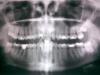

BonyBlu Опубликовано 9 октября, 2007 Поделиться Опубликовано 9 октября, 2007 Добрый день, уважаемые форумчане!!!Проблема в следующем: При обращение к врачу с жалобами на достаточно сильную ночную зубную боль и отек щеки, как с внутренней, так и с внешней стороны был сделан следующий вывод: необходимо удаляь нижнюю левую восьмерку, так как она "растет в челюсть". Операцию надо делать срочно, в стационаре, причем я была предупреждена о непредсказуемости последствий операции, длительном восстановительном периоде и её высокой травматичности. В тот момент был сделан снимок, только беспокоящей меня области. Самостоятельно я сделала панорамный снимок, его и выкладываю. Очень прошу прокомментировать как сам снимок, так и вывод врача. У меня почему-то беспокойство вызывает совсем другая восьмерка??? Ссылка на комментарий

Премоляр Опубликовано 9 октября, 2007 Поделиться Опубликовано 9 октября, 2007 А верхняя 8ка слева вас не беспокоит?Если имеет место боль и коллатеральный отек в обл нижней левой 8ки(перикоронарит),то надо удалять,т.к. в дальнейшем могут наступить осложнения.Не беспокойтесь и не жалейте 8 зуб,т.к. это случается с ними давольно часто-в связи с недостатком места для 8х из-за уменьшения длины зубного ряда в процессе эволюции Ссылка на комментарий

BonyBlu Опубликовано 9 октября, 2007 Автор Поделиться Опубликовано 9 октября, 2007 Да, слева на щеке до сих пор есть отек, правда только внутри и небольшой, и ноющая боль, периодами. А что все таки значит фраза "растет в челюсть" и насколько обоснована необходимость стационара???И еще, если смотреть на картинку (я её зеркально разместила), правая верхняя восьмерка, с ней надо что либо делать, там ничего не болит, по крайней мере пока? Ссылка на комментарий

Штаматолог Опубликовано 9 октября, 2007 Поделиться Опубликовано 9 октября, 2007 Да, слева на щеке до сих пор есть отек, правда только внутри и небольшой, и ноющая боль, периодами. А что все таки значит фраза "растет в челюсть" и насколько обоснована необходимость стационара??? И еще, если смотреть на картинку (я её зеркально разместила), правая верхняя восьмерка, с ней надо что либо делать, там ничего не болит, по крайней мере пока? на мой взгляд удалять Вам нужно как минимум 3 8-ки - обе нижние и верхнюю, которая на снимке справа. Обычно такие операции делают в амбулаторных условиях - ничего суперсложного в них нет. В Вашей ситуации может быть доктор решил перестраховаться и избавить себя от ответственности. Фраза "растет в челюсть" подразумевает, что зубу не хватает места в челюсти и он вряд ли полностью прорежется из-за нависающего края кости над ним. Ссылка на комментарий